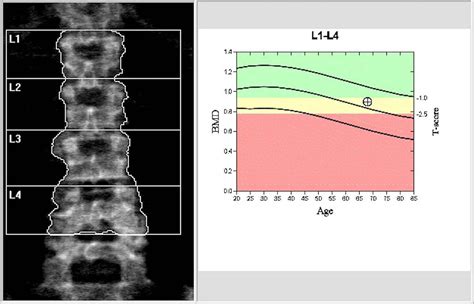

The results of your DEXA scan will be interpreted using a T-score and a Z-score:

Score Interpretation

T-score Compares your bone density to that of a healthy 30-year-old of the same sex. A T-score of -1.0 or higher is considered normal, while a score between -1.0 and -2.5 indicates osteopenia (low bone mass), and a score of -2.5 or lower indicates osteoporosis.

Z-score Compares your bone density to that of an average person of the same age and sex. A Z-score of -2.0 or lower may indicate a need for further medical evaluation.